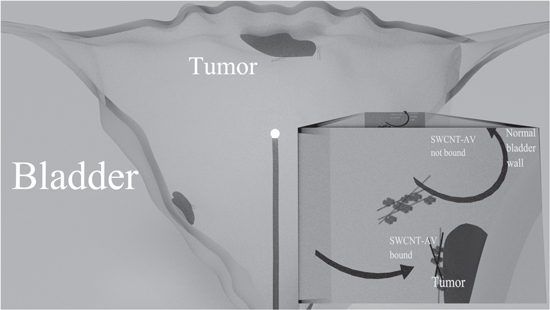

Due to the strong association of AV to bladder tumours and the intrinsic property of nanotubes to absorb NIR light and dissipate energy as heat, this study hypothesises that targeted SWCNT-AVs in combination with a global radiating NIR fibre can be utilised as an alternative to treat NMIBC and reduce relapse rates without invasive surgery (figure 1). This study has proven that SWCNT-AVs specifically target bladder cancer cells in vitro as well as in vivo with no detectable binding to normal urothelium; combining PS-targeted nanotubes with NIR light at relatively low power level resulted in a 50% cure rate with no observable healthy tissue damage for orthotopic MB49 murine bladder tumours, thereby proving the effectiveness and clinical applicability of the proposed approach.

Figure 1. Representation of the structure of the bladder showing the mechanism of the SWCNT-AV and NIR light combination therapy. Cancer targeted SWCNTs are instilled into the bladder via catherization. After a clearance period for unbound nanotubes, a 360° diffusing fibre emitting a 980 nm light is threaded via a catheter into the centre of the bladder. The tumour is irradiated to heat the bound nanotubes and cause cancer cell death.